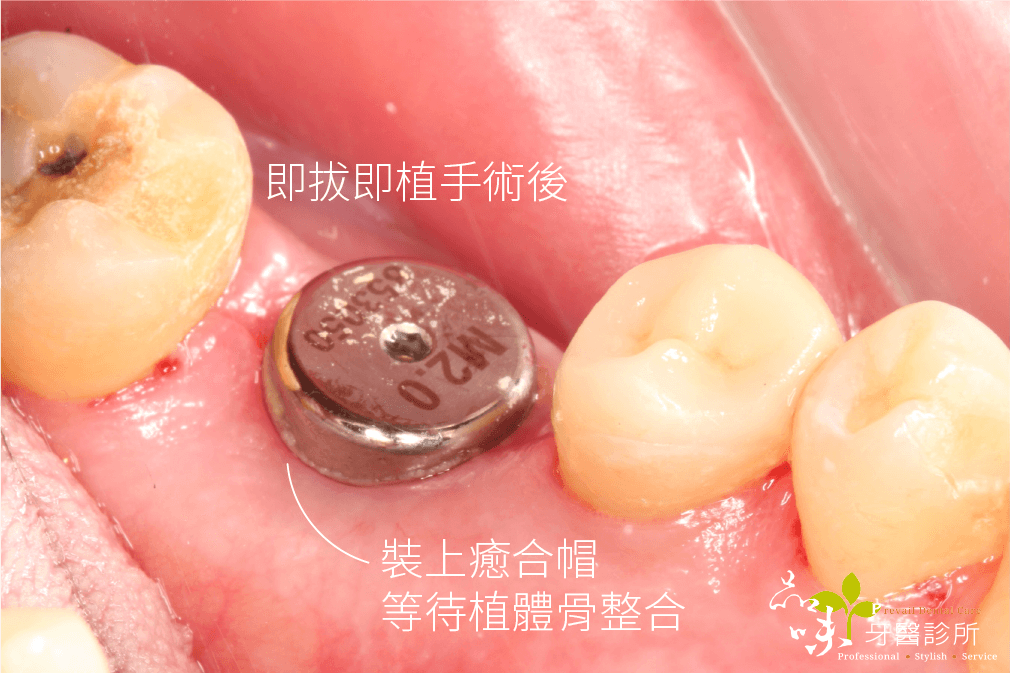

「在牙齒拔除的當次診療中,醫師立即將植體植入乾淨的拔牙窩洞裡,讓拔牙傷口與植體一起癒合」

因為即拔即植是在拔牙當次施作,因此手術傷口比較小,並且不需切開牙齦。如此一來不但可以保存更多骨頭(齒槽骨)與牙肉組織,還能縮短植牙手術的時間,是微創植牙手術的一種。

相對地,即拔即植的療程時間可以縮短許多。醫師在當次門診施行多合一植牙手術,也就是當次門診就完成拔牙、植牙以及補骨手術。由於傷口癒合以及植體的骨整合時間可以同時進行,所以即拔即植的患者缺牙等待時間較短。

文首提到牙裂的陳先生,當天下午就安排了手術。在一系列數位資料蒐集後,進行藍光導航植牙。傍晚陳先生的牙齒就不疼了。

傷口在幾天後再也沒有疼痛感,後續回診追蹤也沒有不舒服。就這樣,四個月很快地過去了,假牙醫師幫他裝好全陶瓷的假牙。現在他可以開開心心地盡情享用美食。